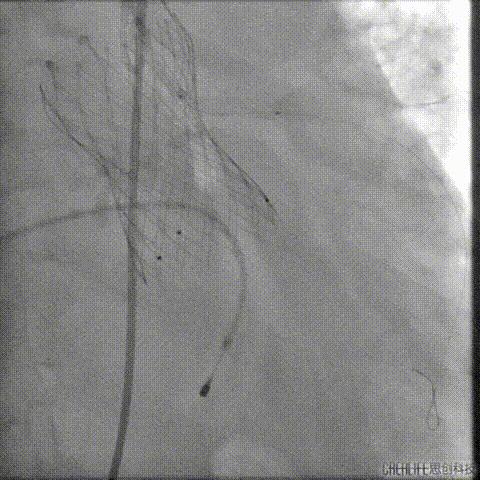

经桡冠脉保护

置入Venus-A32号瓣膜并释放

复查造影

撤出冠脉保护

再次复查造影